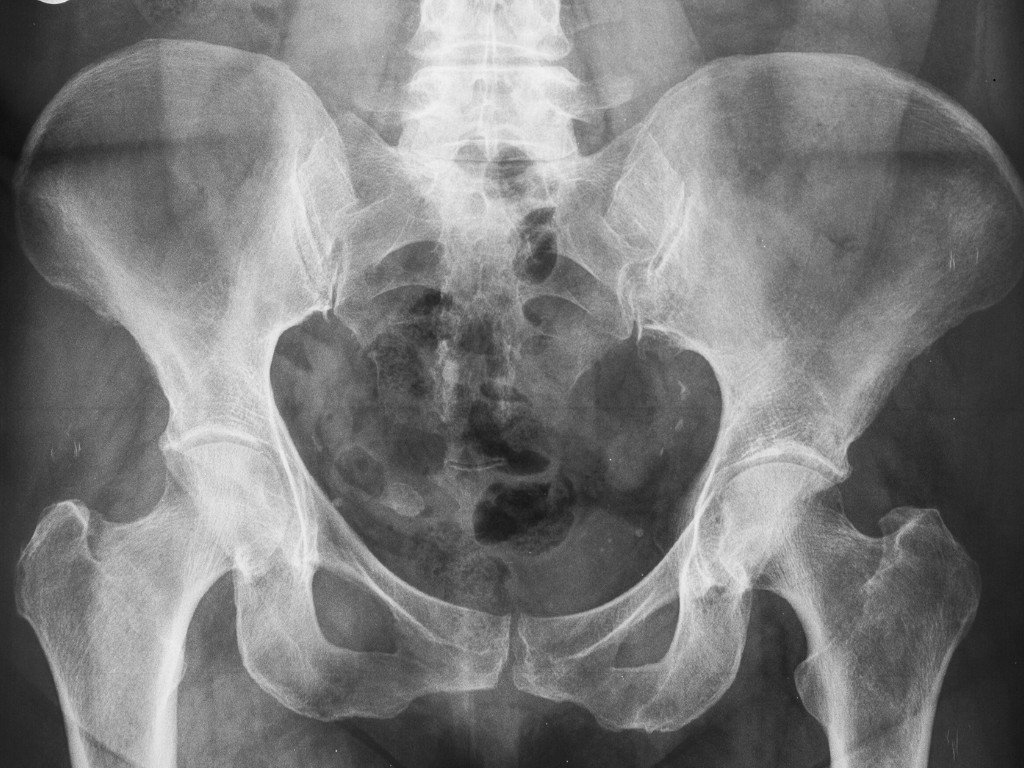

Clear, advanced diagnosis: Using advanced imaging like MRI and X-ray, Dr. Mehta identifies the underlying damage, so your treatment is precise.

Step 3: Investigations

To get a detailed view of your hip health and find the underlying issue, Dr. Mehta may recommend imaging tests like X-rays or an MRI.